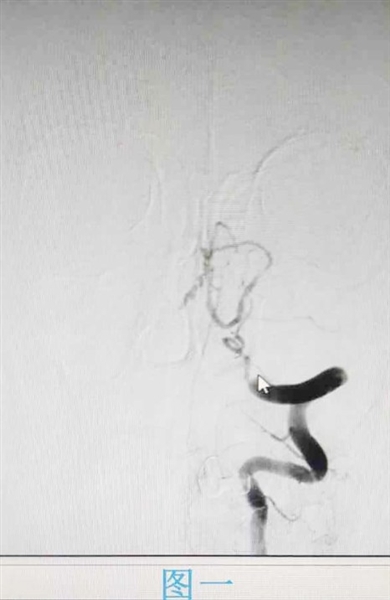

2023年11月30日,27岁患者李猛(化名)因出现中风症状,已不能自行行走和说话。在家人的陪同下,李猛被紧急送到城阳区人民医院急诊神经内科。神经内二科医生一边和家属说明情况,一边开启卒中绿色通道进行诊断检查,并和家属沟通说明检查及治疗的必要性和风险性。经脑核磁所示,李猛被确诊为急性脑梗死,左侧大脑中动脉闭塞。由于已过静脉溶栓时间窗,医生决定进行介入手术,给予其脑动脉内溶栓治疗。在江毅和团队的努力下,李猛成功脱险,言语功能已明显改善,能部分发音。

江毅介绍,在卒中中心接诊的患者中,也有不少脑血管重度狭窄的病人。患者张磊因头晕入院,医生对其进行相关检查,通过颈部血管超声显示,张磊左侧锁骨下动脉盗血,完善脑血管造影显示双侧颈内动脉及左侧锁骨下动脉重度狭窄。经过介入支架手术治疗后,张磊恢复良好并出院。